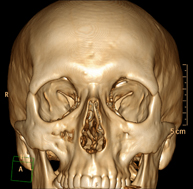

Prova radiològica que consisteix en obtenir imatges del massís facial (cara) d'alta definició anatòmica, mitjançant l'ús d'un equip de TC (Tomografia Computeritzada). Indicacions: tumors, cirurgia plàstica. - TC Oïda

Prova radiològica que consisteix en obtenir imatges del crani d'alta definició anatòmica (tronc cerebral, cerebel, cervell, calota cranial, etc. ) mitjançant l'ús d'un equip de TC (Tomografia Computeritzada). Indicacions: traumatismes, cefalea, trastorns de la memòria, pèrdua de força sobtada en una extremitat o meitat del cos. - TC Coll